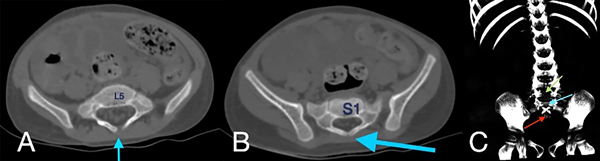

En la tomografía se evidenció presencia de S1-S2 con ausencia del resto de cuerpos sacro-coxígeos, así como hipodensidad a nivel de la médula que podría sugerir siringomielia (Figura 1). También se encontró falta de unión de algunos elementos posteriores a nivel de L5-S1 (Figura 2), lo que sugiere el diagnóstico de síndrome de regresión caudal asociado a probable siringomielia y probable vejiga neurogénica dado engrosamiento marcado de las paredes vesicales (Figura 3). Además, se encontró dilatación ureteropielocalicial de forma bilateral (Figura 4). A raíz de estos hallazgos, se solicitó una valoración por genética clínica, la cual determinó que la paciente cumple con los criterios clínicos de regresión caudal y tiene antecedentes de diabetes gestacional insulino-dependiente, lo cual es un factor de riesgo.

Figura 1. Tomografía de abdomen simple en ventana ósea, reconstrucciones sagital (A), coronal (B) y 3D (C), mostrando la presencia de vertebras sacras 1 y 2, con ausencia del restante de los elementos óseos sacro-coxígeos (flechas azules).

En este caso, se encontró una ausencia parcial sacro coxígea con preservación de S1 (Figura 1), asociada a no unión de elementos posteriores de L5 y S1 (Figura 2), siendo un síndrome de regresión caudal tipo I según Pang, asociado a alteraciones genitourinarias dadas por hidronefrosis bilateral (Figura 3) y engrosamiento de las paredes vesicales (Figura 4).